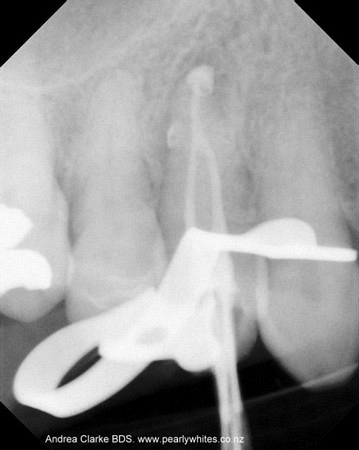

A root canal or filling is a sequence of treatments ( 1-2 appointments) resulting in the elimination of infection and protection of the decontaminated tooth from future bacterial invasion. The inflamed or infected tooth pulp (made of nerve tissue, blood vessels and other cellular entities) is removed, cleaned and disinfected, then filled and sealed with gutta-percha, a rubber-like inert filling material.

See xrays of before and after a root canal is completed below